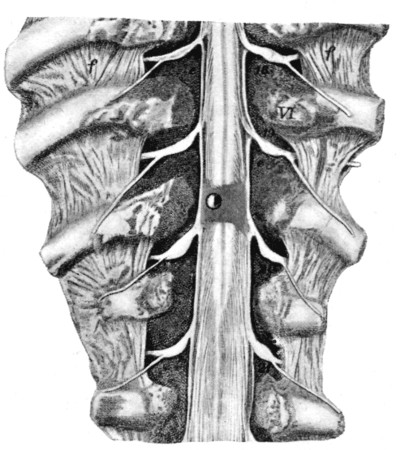

79. Contused Spinal Cord 333

80. Divided Spinal Cord 334